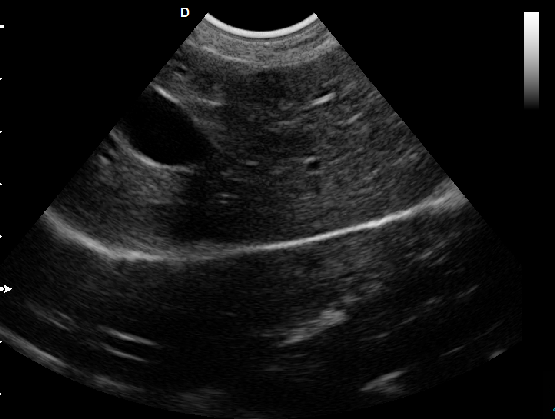

P5-VET手提式獸用彩超機心臟超聲檢查圖

心臟超聲檢查:

心臟超聲是唯一能動態顯示心腔內結構、心臟的搏動和血液流動的儀器,對人體沒有任何損傷。心臟的各個結構清晰地顯示在屏幕上。通過彩超的測量,醫生可了解瓣膜病變的程度以決定保守治療還是手術治療。心肌的增厚、心腔的擴大都要依賴彩超來判斷;對冠心病,彩超能直觀顯示心肌的運動狀況及心功能,向臨床醫生提示心肌缺血的部位。